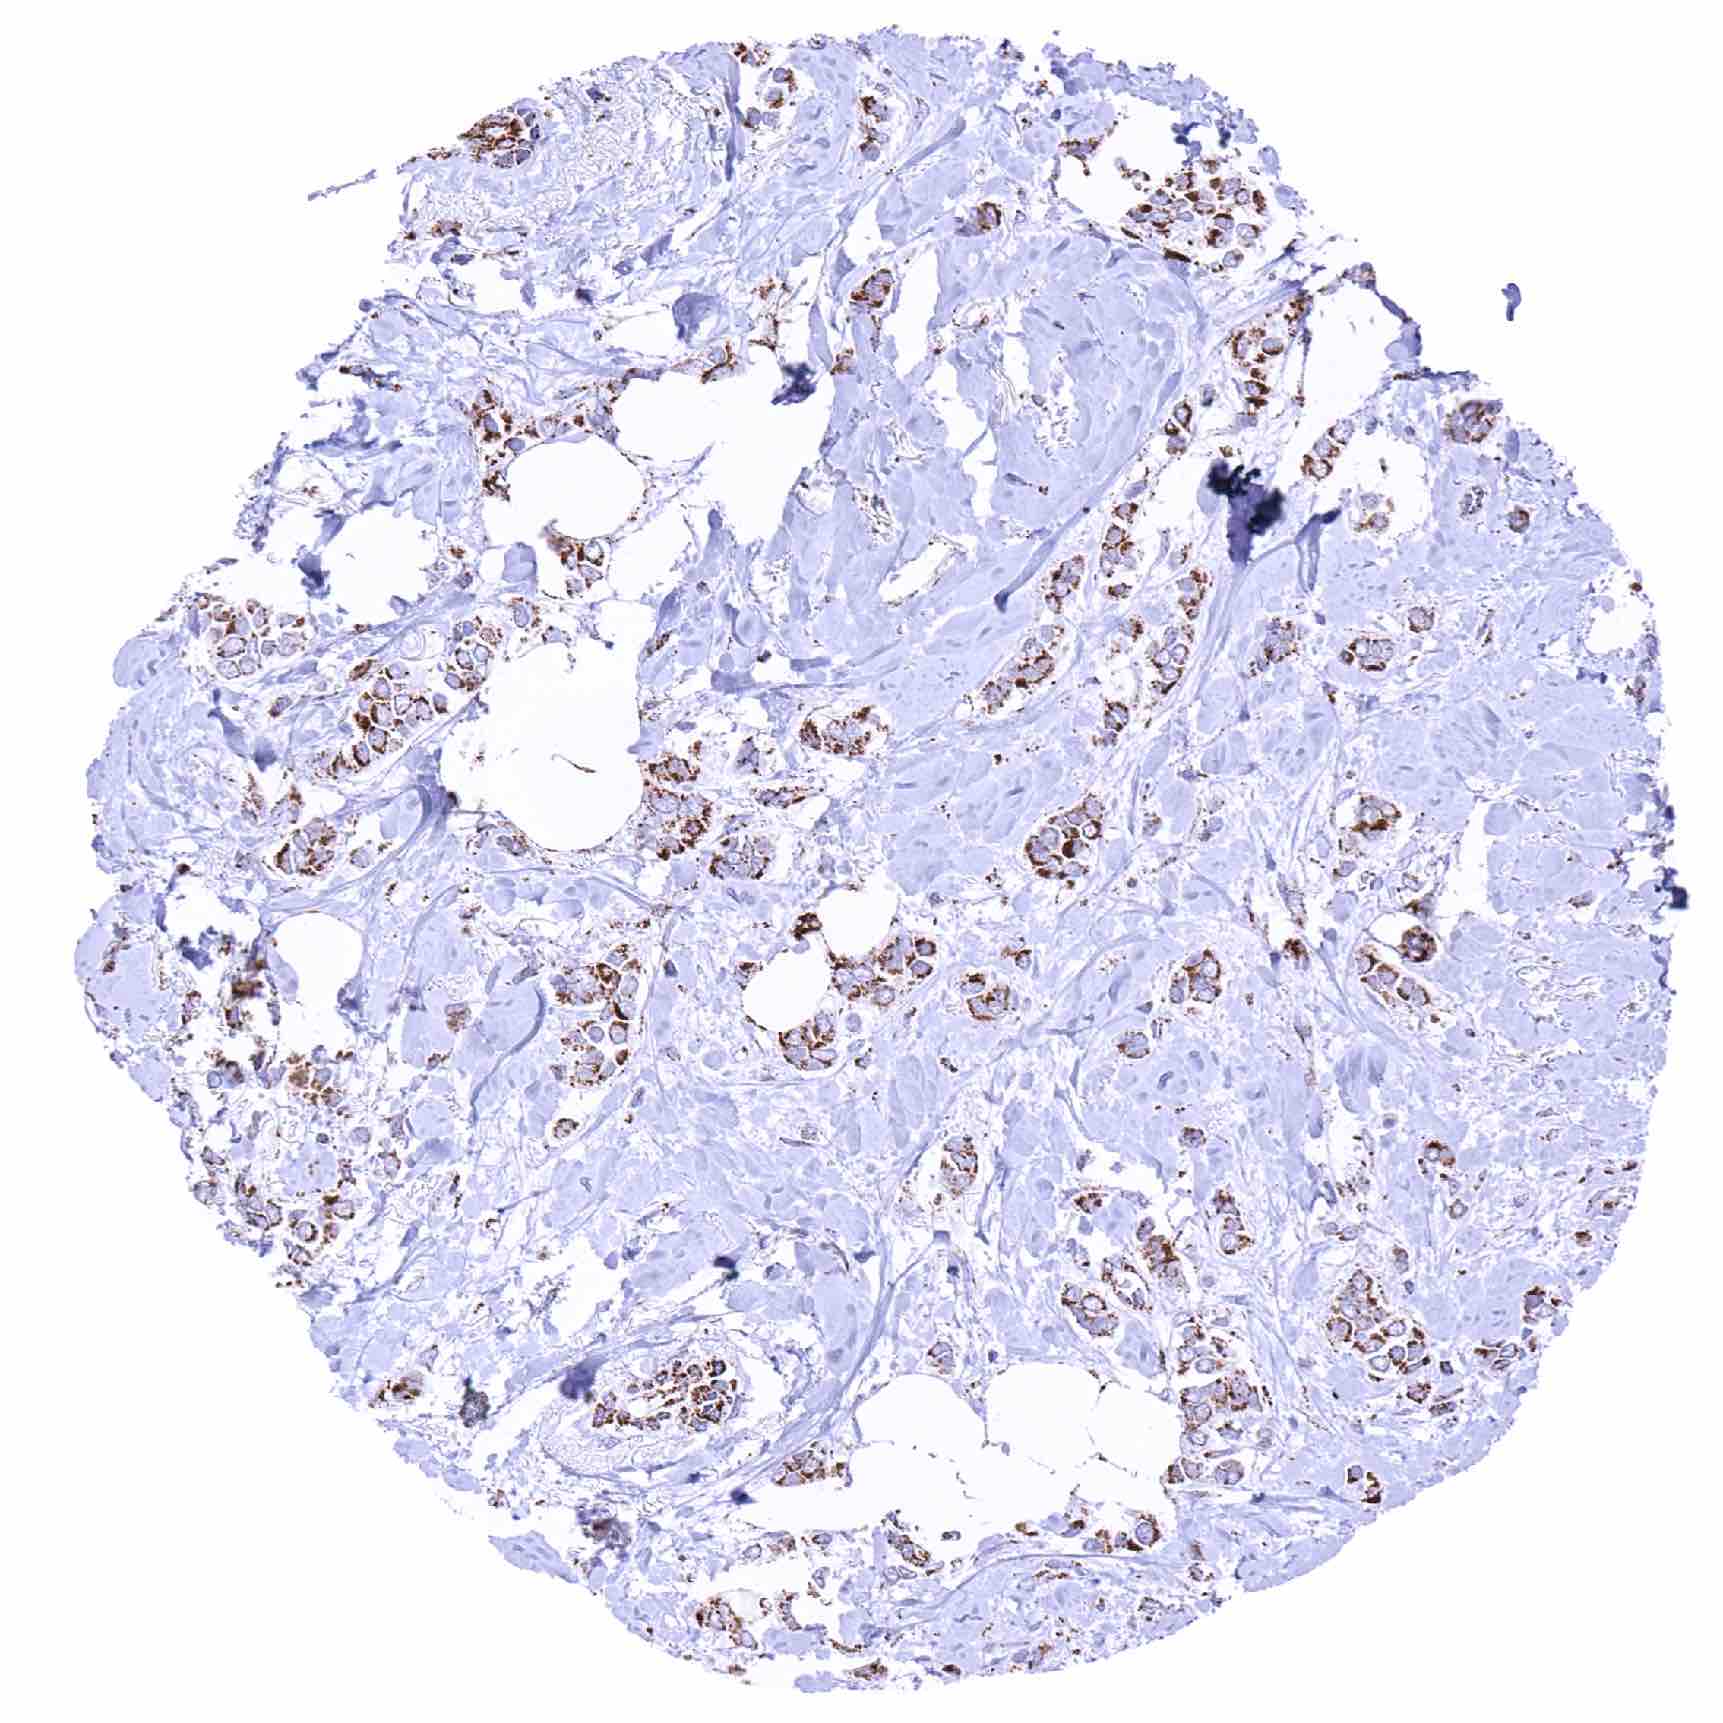

Pancreas – SDHA negative neuroendocrine tumor